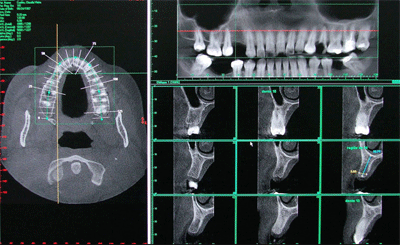

I-CAT Vision

I-CAT Vision é um software que gera imagens, onde integram módulos de visualização para ATM, implante e todos os cortes axiais, coronais e sagitais.